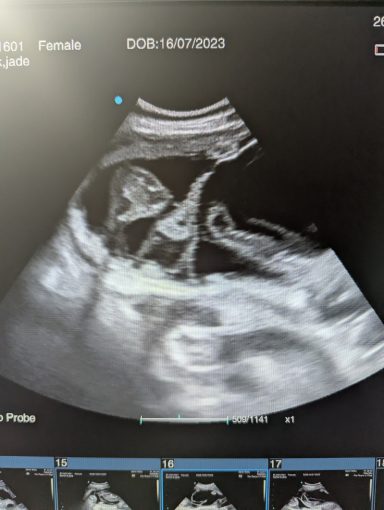

Ultrasound pregnancy scanning is a safe, non-invasive way to confirm pregnancy in dogs and cats, offering breeders and pet owners peace of mind and vital information to support responsible care. It allows us to detect gestational sacs, assess foetal development, and estimate litter size—all while ensuring the wellbeing of the animal.

Pregnancy can sometimes be detected as early as Day 18 post-mating, but scanning at this stage is not routinely recommended. Embryos are still developing and may not be clearly visible, and there is a natural risk of embryo resorption, which can lead to misleading or inconclusive results.

For the most accurate and reliable scan, we advise booking between Day 25 and Day 32, when pregnancy is more easily confirmed and foetal structures are clearer. If an early scan is performed and no pregnancy is detected, we offer a FREE complimentary re-scan after 7 days at the clinic to ensure clarity and support informed decision-making.